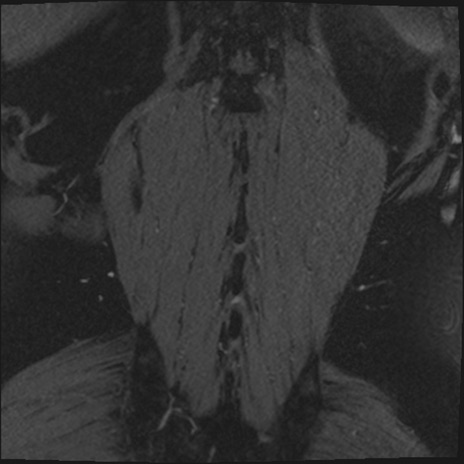

【整形】TIPS症例2 腰椎MRI 3D(冠状断像)

【症例】70歳代男性

【主訴】左下肢痛

【現病歴】2週間前くらいから腰痛、左下肢痛あり。左臀部から大腿、下腿外側のしびれが常時ある。歩行とともに同部位の痛みあり。

【身体所見】Lasegue70-/60+、Bragard-/±、PTR ±/±、ATR -/-、IP 5/5、TA 5/4、TS 5/5、EHL 右第1足趾なし/3、FHL 5/5、hypersthesia(-)、足背動脈触知良好

異常所見と診断は?